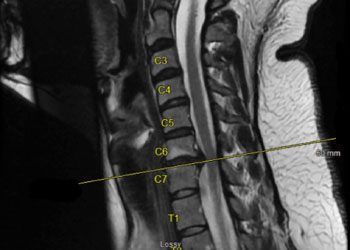

Artificial DiscReplacement Feature

Fusionless Cervical Spine Surgery for Herniated Disc

October 27, 2021